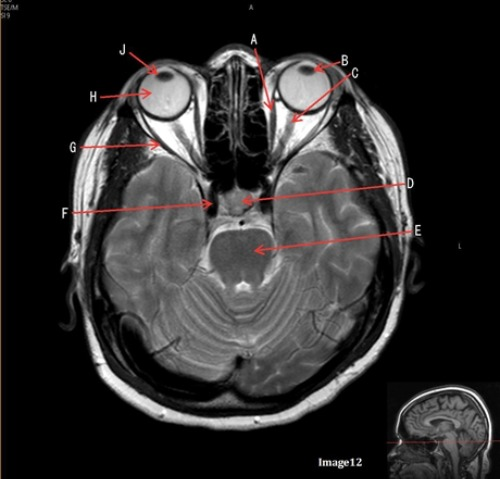

Letter G in Image 12 is pointing to:

A. Lens

B. Lateral rectus muscle

C. Medial rectus muscle

D. Internal carotid artery

E. Globe

Letter C in image 12 is pointing to:

A. Left optic nerve

D. Lens

E. Midbrain

Letter D in Image 12 is pointing to:

A. Optic nerve

B. Pituitary gland

C. Globe

Letter E in Image 12 is pointing to:

D. Pons

E. Left lens

Letter A in image 12 is pointing to:

Letter H in Image 12 is pointing to:

Letter B in Image 12 is pointing to:

Letter J in Image 12 is pointing to:

A. Globe

D. Right lens

Letter F in Image 12 is pointing to: